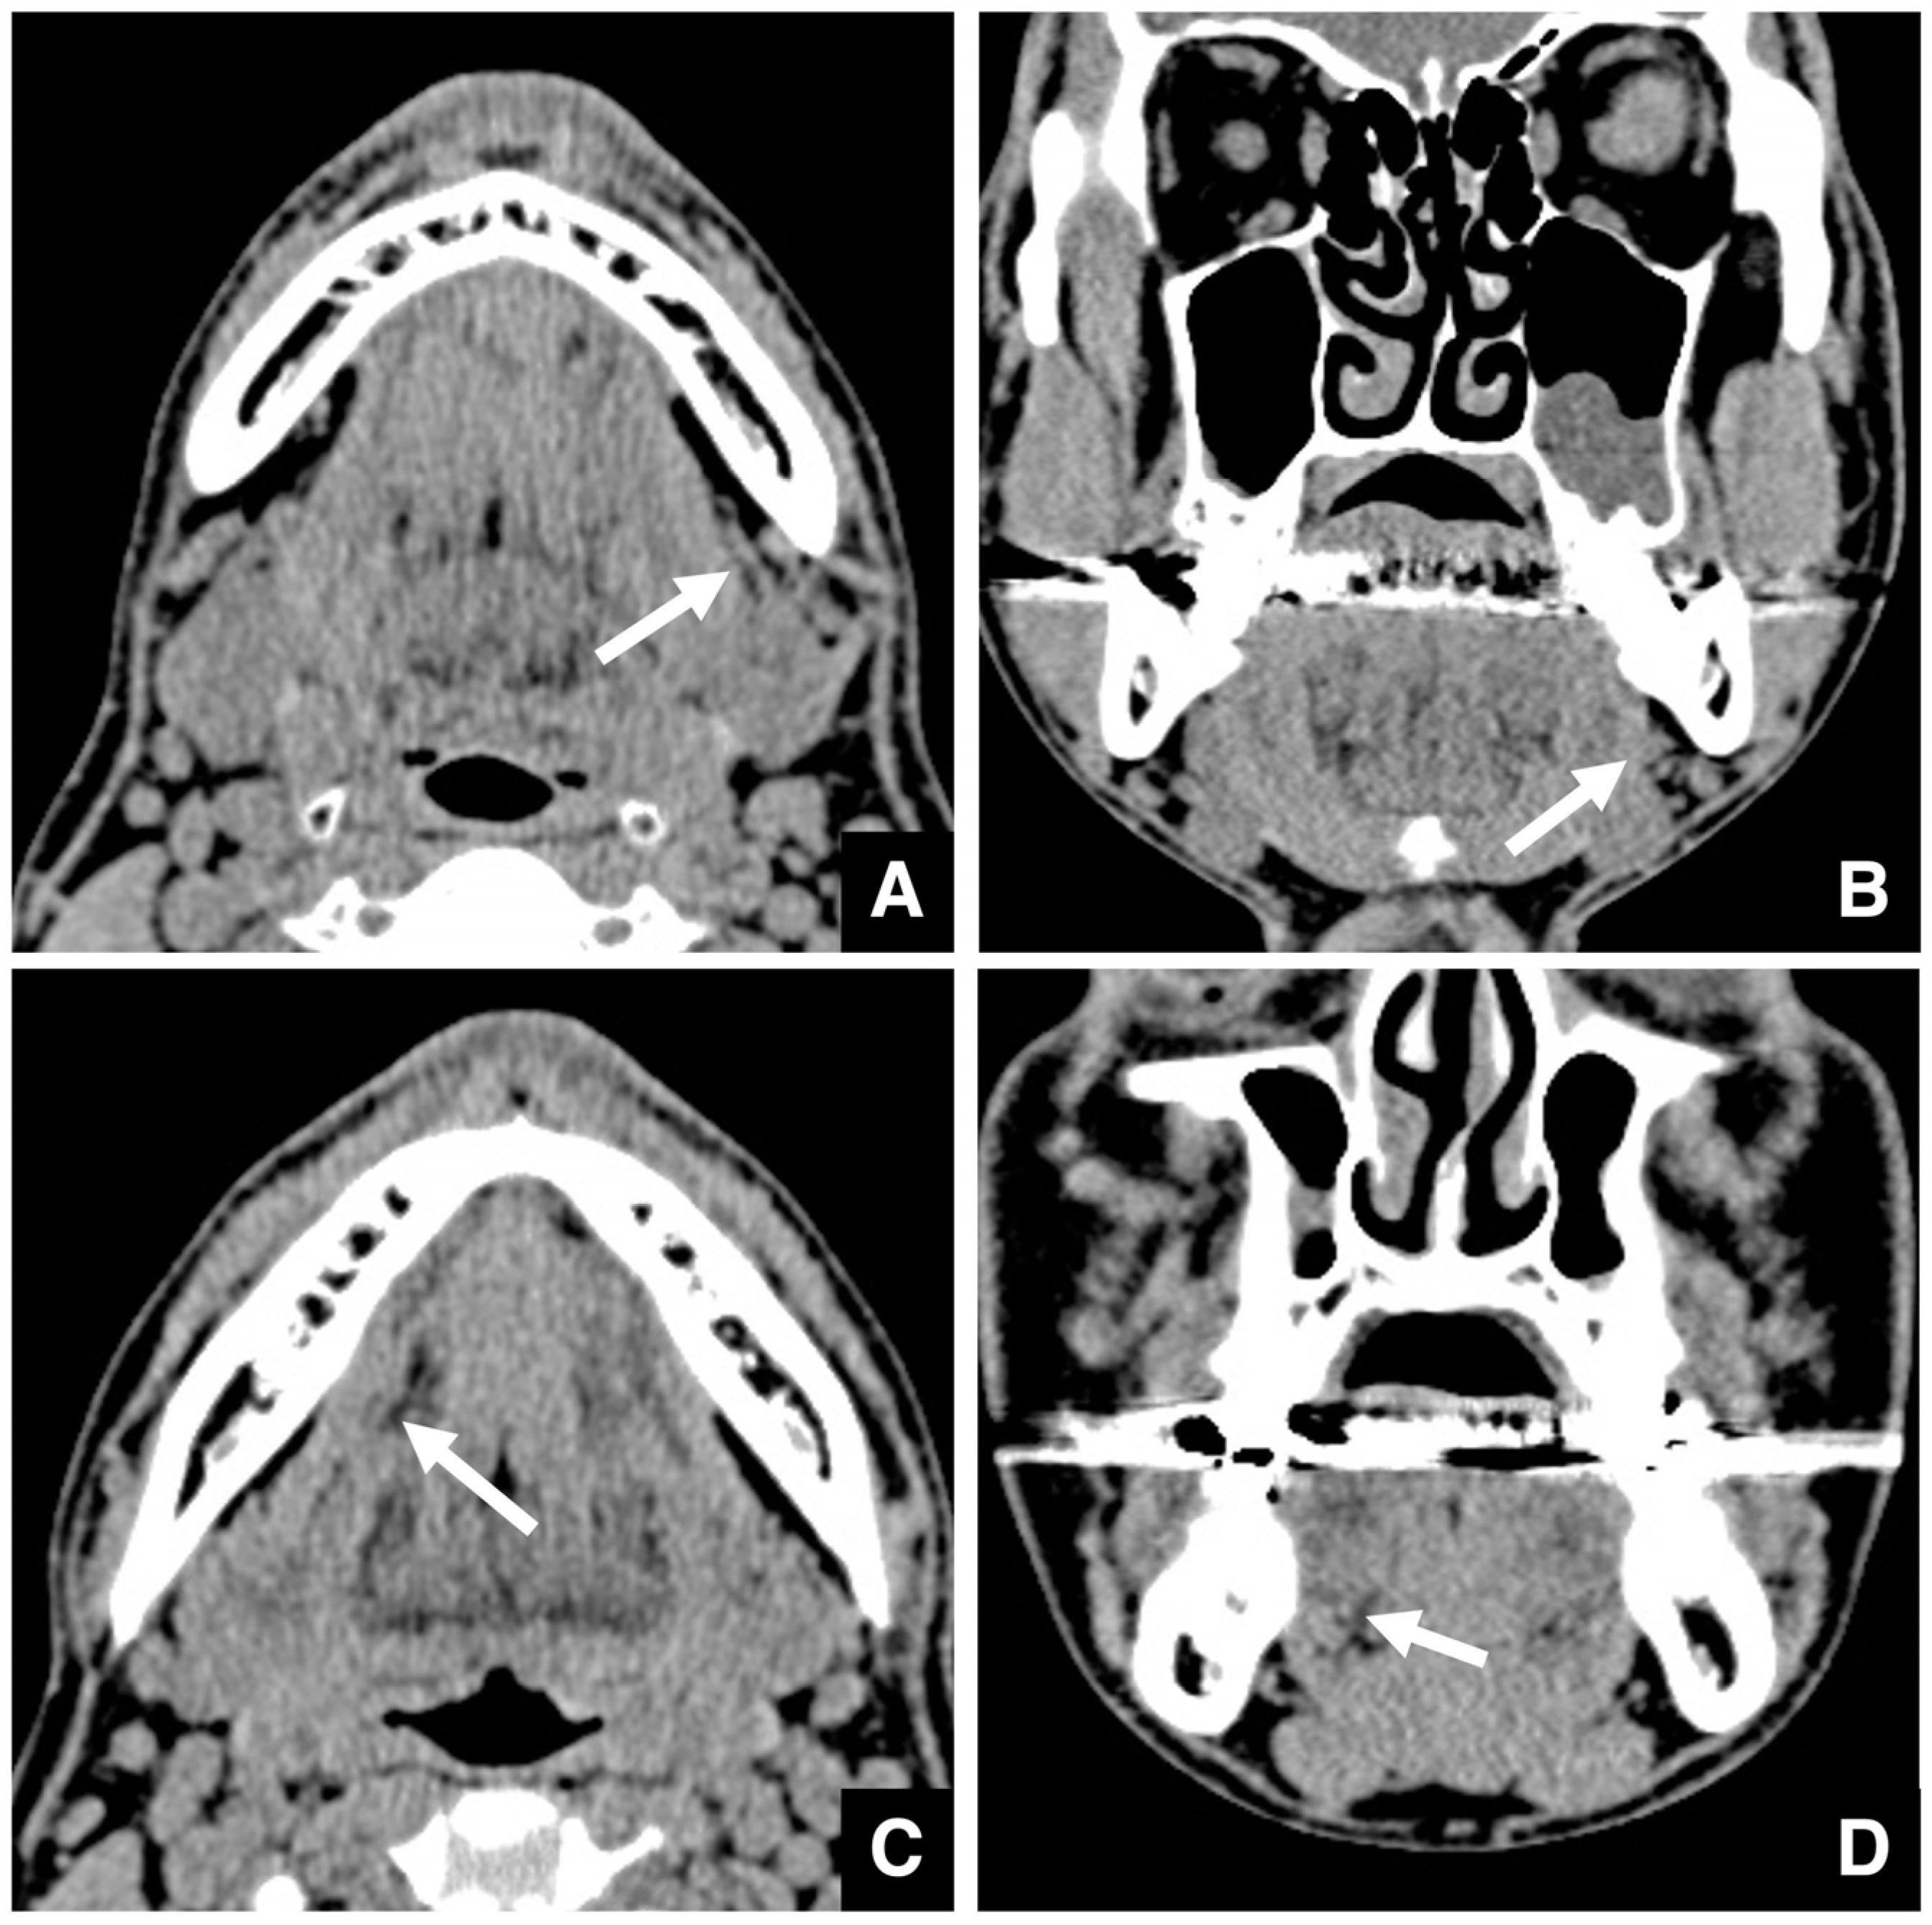

| Improving safety through prediction of surgical difficulty and complication 1. Circumstance of pterygoid venous plexus Carefully observe the fat tissue surrounding the medial and lateral pterygoid muscles to assess the development of the internal vascular structures (using CT and MR to evaluate the size of the fat tissue) 2. Fusion status of the maxillary tuberosity and pterygomaxillary suture When the fusion is narrow and the degree of calcification (CT number) is low or when the fusion is wide and high 3. Course of the descending palatine artery and thickness of surrounding bone When the palatal canal wall is thick, the probability of damage during transection is low. When it is thin, the possibility of damage cannot be ruled out. Setting the osteotomy line 1. Distance from the piriform rim to the greater palatine canal Long, short, cortical bone thickness, presence or absence of bone irregularities 2. Evaluation of the size, morphology, and internal features (mucosa, septa, etc.) of the maxillary sinus Size, shape, presence or absence of septa, presence or absence of masses, presence or absence of mucosal thickening 3. Relationship between the floor of the maxillary sinus and the apices of the molars Describe the maxillary sinus floor and the apex of each molar tooth 4. Presence of nasal septal deviation, size of the nasal passages, and thickness of the lateral nasal wall bone Presence or absence of nasal septal deviation, Size of the nasal passage, Thickness of the cortical bone of the lateral wall 5. Course of the mandibular artery The course from the pterygoid cleft to the pterygopalatine fossa in the posterior maxilla |